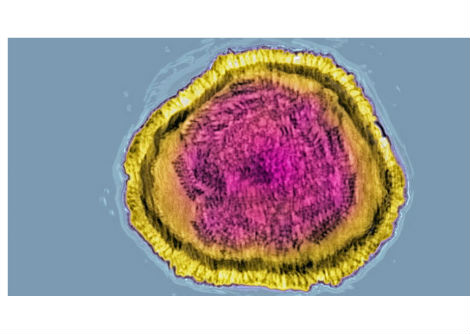

علاوة على ذلك ، وُجد أن زيادة الوزن في كل من الطفولة وصغار البلوغ تزيد من خطر الإصابة بالجلطات الشريانية - أي الجلطات الناتجة عن ضيق الأوعية الدموية مع الترسبات الدهنية والالتهابات . نظرًا لوجود عدد قليل من حالات جلطات الدم الشرياني في الدراسة ، هناك حاجة إلى مزيد من الدراسات لتأكيد هذه النتائج . تم إجراء جميع المقارنات في الدراسة مع المجموعة الضابطة ، التي كان وزنها طبيعيًا في كل من 8 و 20 عامًا .